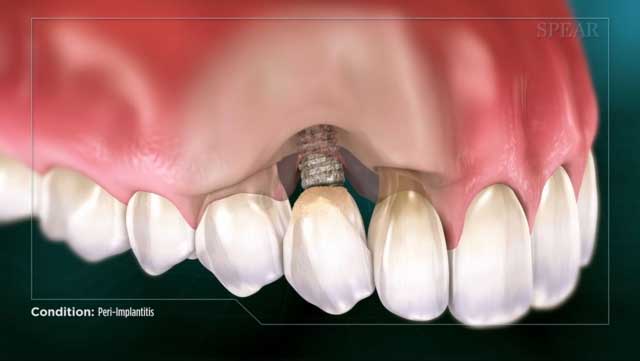

- Targeted Treatment: Specifically treats peri-implantitis by addressing infection and inflammation around dental implants.

LAPIP (Laser Assisted Peri-Implantitis Procedure) is a minimally invasive laser treatment designed to address peri-implantitis, a condition involving infection and inflammation of the tissue and bone around dental implants. Using the PerioLase MVP-7 laser, LAPIP removes infected tissue, eliminates bacteria, and stimulates tissue and bone regeneration to promote implant stability. It offers a less invasive, cost-effective alternative to traditional surgery or implant replacement.

- Laser Targeting: The PerioLase MVP-7 laser precisely targets and removes infected tissue and bacteria in gum pockets surrounding the implant.

- Bacterial Removal: The laser vaporizes bacteria and contaminants, creating a clean environment for healing.

- Tissue Regeneration: Stimulates the growth of healthy tissue and supports bone regeneration around the implant.